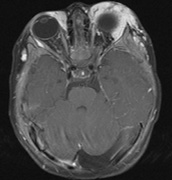

NEUROLOGIC FINDINGS.

1. Schwannomas most commonly affect the fifth cranial nerve (CN), but any cranial nerve may be affected. In contrast to vestibular schwannomas (CN VIII), these typically do not grow large.84,90 Vestibular schwannomas (acoustic neuromas) are the classic finding in NF2 (Fig. 7). The risk for malignant transformation is low, but may be higher with radiation exposure.84,94

3. Other tumors: low-grade ependymomas and gliomas may affect the cervical spine and Brainstem (Fig. 7).84

Fig. 7. Neurofibromatosis type 2: Images of a 12-year-old boy with deafness and weakness in his arms and legs, whose father has bilateral deafness. Axial T2-weighted (a) and postcontrast axial (b) T2-weighted images reveal bilateral vestibular schwannomas, which are also known as acoustic neuromas (arrows). This is the classic finding of NF2. (b, c) Bilateral schwannomas are seen in Meckel's cave (arrowheads) and a (d) lower left cranial nerve schwannoma extends into the pars nervosa of the jugular foramen (arrow). (e) A part cystic and part solid enhancing ependymoma in seen within the cervical cord and medulla and within the distal cord and conus. (e, f) Thoracic schwannomas are present at numerous levels (arrowheads). Marked enhancement and thickening of the roots within the cauda equina also represent multiple schwannomas.